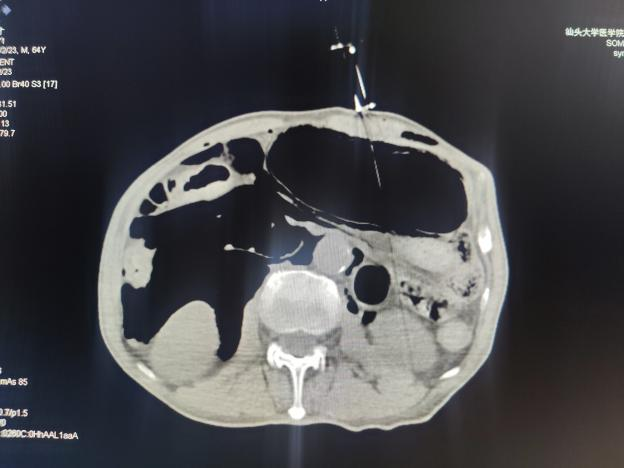

近日, 微创介入科易长虹副主任团队成功开展CT引导下经皮胃造瘘技术,为粤东地区首例成功通过此术式为患者打通生命营养通道。

2024年2月,新年伊始, 大学路院区微创介入科门诊收治了一位64岁下咽鳞癌患者。

因为肿瘤病灶,患者出现呼吸、进食困难,为患者做气管造口及留置空肠营养管,后续行多程化疗联合免疫治疗、放疗。但因空肠营养管脱落2天,收住院入院时病人已禁食48小时以上,身体十分虚弱。

关键时刻,肿瘤医院微创介入科易长虹副主任经评估后决定为患者行CT引导下经皮胃造瘘术。术程顺利,术中创伤小,术后24小时即可喂食,成功为患者解决饮食营养问题,提高生活质量。

CT引导下经皮胃造瘘术是一种特殊的管饲营养方法,主要用于经口摄食困难而又有正常胃肠功能的病人。这项技术主要是在CT引导下,经腹部皮肤穿刺放置胃造瘘管,营养物质通过造瘘管直接注入胃内,为需长期管饲营养支持的病人提供另一种进食方法。